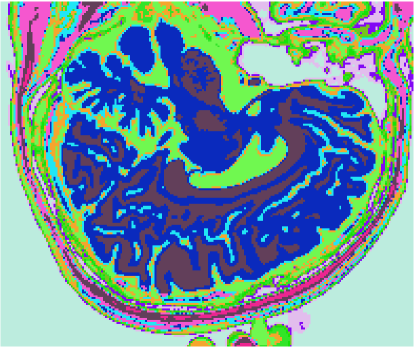

3.1 Classificadores Dialéticos Objetivos

A figura 6 mostra os resultados de classificação, enquanto a figura 7 exibe os resultados de quantização para a imagem sem ruído da fatia 97, figura 5, usando os métodos KO, CM, KM, ODC-PME e ODC-CAN. Esses resultados ilustram qualitativamente as diferenças entre os métodos de classificação e quantização, dado que a fatia 97 possui todas as 13 classes presentes na análise [51].

Figura 6: Composição colorida R0-G1-B2 das imagens da fatia 97 ponderadas em PD, T1subscript𝑇1T_{1} e T2subscript𝑇2T_{2} (a) e resultados de classificação usando os métodos KO (b), CM (c), KM (d), ODC-PME (e) e ODC-CAN (f)

A tabela 2 mostra os resultados da avaliação dos métodos de classificação não supervisionada quanto à quantização vetorial, usando os índices de fidelidade ϵMEsubscriptitalic-ϵME\epsilon_{\textnormal{ME}}, ϵMAEsubscriptitalic-ϵMAE\epsilon_{\textnormal{MAE}}, ϵMSEsubscriptitalic-ϵMSE\epsilon_{\textnormal{MSE}}, ϵRMSEsubscriptitalic-ϵRMSE\epsilon_{\textnormal{RMSE}} e ϵPSNRsubscriptitalic-ϵPSNR\epsilon_{\textnormal{PSNR}}, considerando todas as 181 fatias com 3 bandas (DP, T1subscript𝑇1T_{1} and T2subscript𝑇2T_{2}), para os métodos KO, CM, KM, ODC-PME e ODC-CAN e 0% de ruído. Já os gráficos das figuras 8, 9, 10 e 11 mostram os resultados em função do nível percentual de ruído para os diversos métodos, para um total de 6 volumes de 181 fatias de 3 bandas, totalizando 1086 imagens coloridas, ou 3258 imagens em níveis de cinza.

Figura 7: Composição colorida R0-G1-B2 das imagens da fatia 97 ponderadas em PD, T1subscript𝑇1T_{1} e T2subscript𝑇2T_{2} (a) e resultados de quantização usando os métodos KO (b), CM (c), KM (d), ODC-PME (e) e ODC-CAN (f)